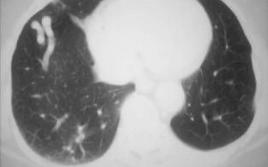

1.分葉狀圓形或橢圓形病灶,邊緣可見有異常血管與肺門相連的“血管蒂征”(圖8-2-3A8-2-3B8-2-3C8-2-3D8-2-3E8-2-3F)。

螺旋CT及電子束CT(EBCT)是診斷PAVMs的一種有效手段。隨PAVMS類型的不同,CT表現有所不同。單發或多發具有瘤囊者平掃可顯示大小不等呈中等密度的圓形、橢圓形或分葉多囊狀影,CT值與血管一致。明顯者可見與其相連的迂曲、擴張的血管影。增強後瘤囊迅速強化,峰值與右心-肺動脈充盈期一致。至左心期強化程度下降。同時,還觀察到供血、引流的肺動、靜脈,“團注”的速度增強掃描效果更好。多發或瀰漫型PAVMS主要右下葉表現眾多小結節網狀結構,造影可見增強和擴張的血管影,但很難看到動、靜脈的連通。Remy等研究發現對比增強EBCT在PAVMs的正確診斷及解剖結構顯示方面明顯優於肺動脈造影。